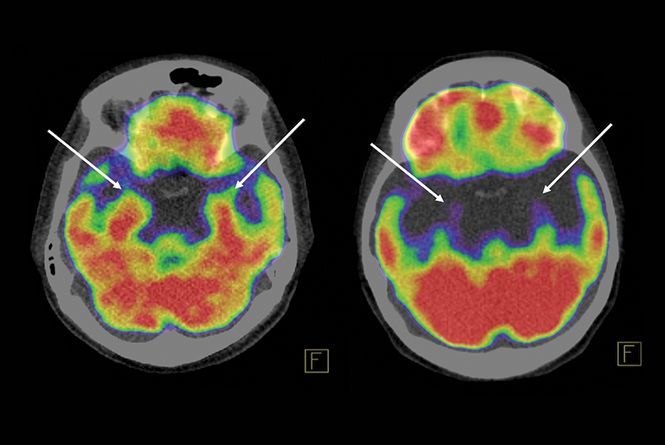

Abohashem and his colleagues retrospectively analyzed full-body PET/CT scans from 104 patients, most of whom had cancer and 41 of whom had developed TTS since first being scanned, and 63 individually matched controls. The team calculated ratios of the activity in each person’s amygdala to that of two brain regions that attenuate the stress response, the temporal lobe and the prefrontal cortex. Higher amygdala activity was associated with an increased risk for TTS, and among those with the condition, patients with higher ratios had developed TTS roughly two years earlier following the imaging than those with lower ratios. “We can now show that this syndrome happens as a result of chronic stress over years that makes you vulnerable to developing the syndrome more easily and sooner than [less stressed] people,” Abohashem says.